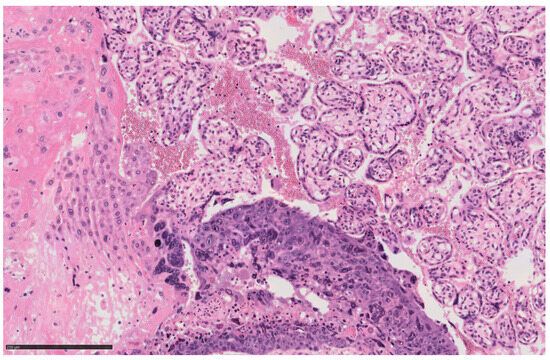

Massive Fetomaternal Hemorrhage Caused by an Intraplacental Choriocarcinoma: Case Report and Review of the Literature

2. Case Description